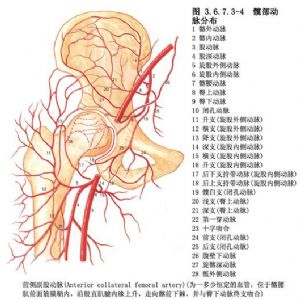

手術相關解剖見下圖(圖3.6.7.3-1~3.6.7.3-4)。